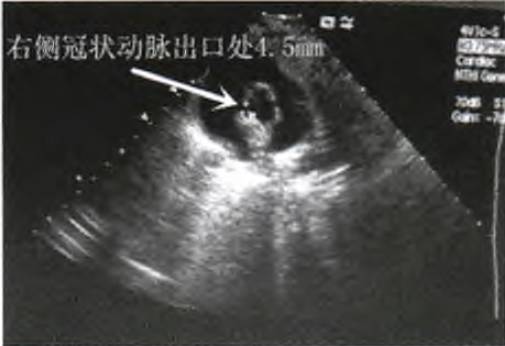

入院后予氨曲南抗感染,甘草酸二铵营养肝功能。患儿仍反复高热,咽部充血明显,双侧扁桃体I度肿大,右侧扁桃体可见白色块状分泌物,双侧颈部可扪及肿大淋巴结,脾脏肿大,伴肝功能损害,结合白细胞计数及淋巴细胞数较入院前明显升高,需警惕EB病毒感染,急查EB病毒抗体。患儿仍高热,双结膜充血,颈部可扪及肿大淋巴结,双足背及趾端稍肿胀,不能除外川崎病,行心脏彩超检查,结果回报:左侧冠状动脉出口处3.2 mm,右侧冠状动脉出口处4.5 mm(图1),患儿冠状动脉扩张明显。

图1 患儿入院次日心脏彩超左、右侧冠状动脉扩张改变

患儿入院次日心脏彩超检查结果示左侧冠状动脉出口处3.2 mm,右侧冠状动脉出口处4.5mm,根据冠脉扩张性病变诊断标准,双侧冠状动脉均扩张,右侧明显,虽患儿无口唇潮红、皲裂,无杨梅舌,无掌、跖面潮红,但结合患儿反复高热,双结膜充血,颈部可及肿大淋巴结,双足背及趾端稍肿胀,考虑不完全川崎病(Kawasaki disease,KD),给予丙种球蛋白联合阿司匹林治疗。